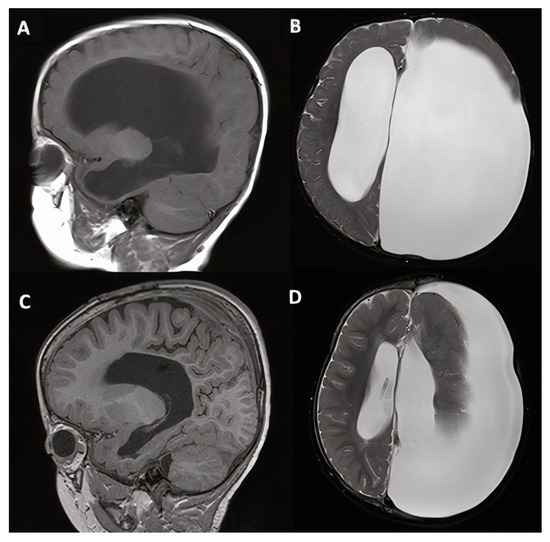

3.1.2. Case #2. Congenital Hydrocephalus with Cerebral Palsy

| 2 | 17 m, M |

|